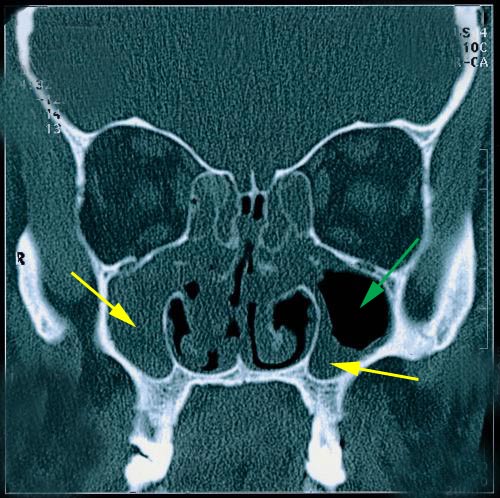

Im CT sieht der Arzt dann keinen dunklen Fleck mehr (=Luft=so soll es sein=gesund) (grüner Pfeil), sondern er sieht einen grauen Schlier (gelber Pfeil) … entweder die Kieferhöhlenschleimhaut ist ganz zu wie in diesem Bild links, oder die Schleimhaut ist verdickt – rechts zu sehen.